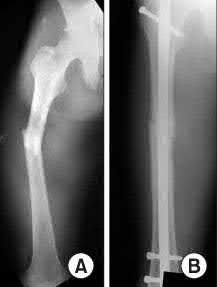

A 35-year-old-male sustains the fracture seen in Figure A. Which of the following reduction forces must be applied to the proximal fragment to correct the deformity commonly seen in these fractures?

Figure A demonstrates a displaced subtrochanteric femur fracture with an intact lesser trochanter. The pull of iliopsoas on the lesser trochanter as well as the intact external rotators and gluteal musculature results in the the proximal fragment being in a flexed and externally rotated or abducted position (the most common post operative deformity). Reduction manuevers must be biologically friendly but also counteract the flexion/abduction moment. Lundy's review article discusses evaluation and treatment of subtrochanteric fractures. The review article details the various implants often used which include 95 degrees plates, femoral reconstruction nails, or trochanteric femoral nails with interlocking options. Lundy's article discourages the use of the 135 degree screw and side plate combo due to high failure rates in these fracture patterns. Bedi et al also review treatment of these fractures and discuss common

problems of malunion, nonunion, and implant failure. The article reviews reduction techniques that are soft tissue friendly, as well as the use of appropriate implants in these fracture types.